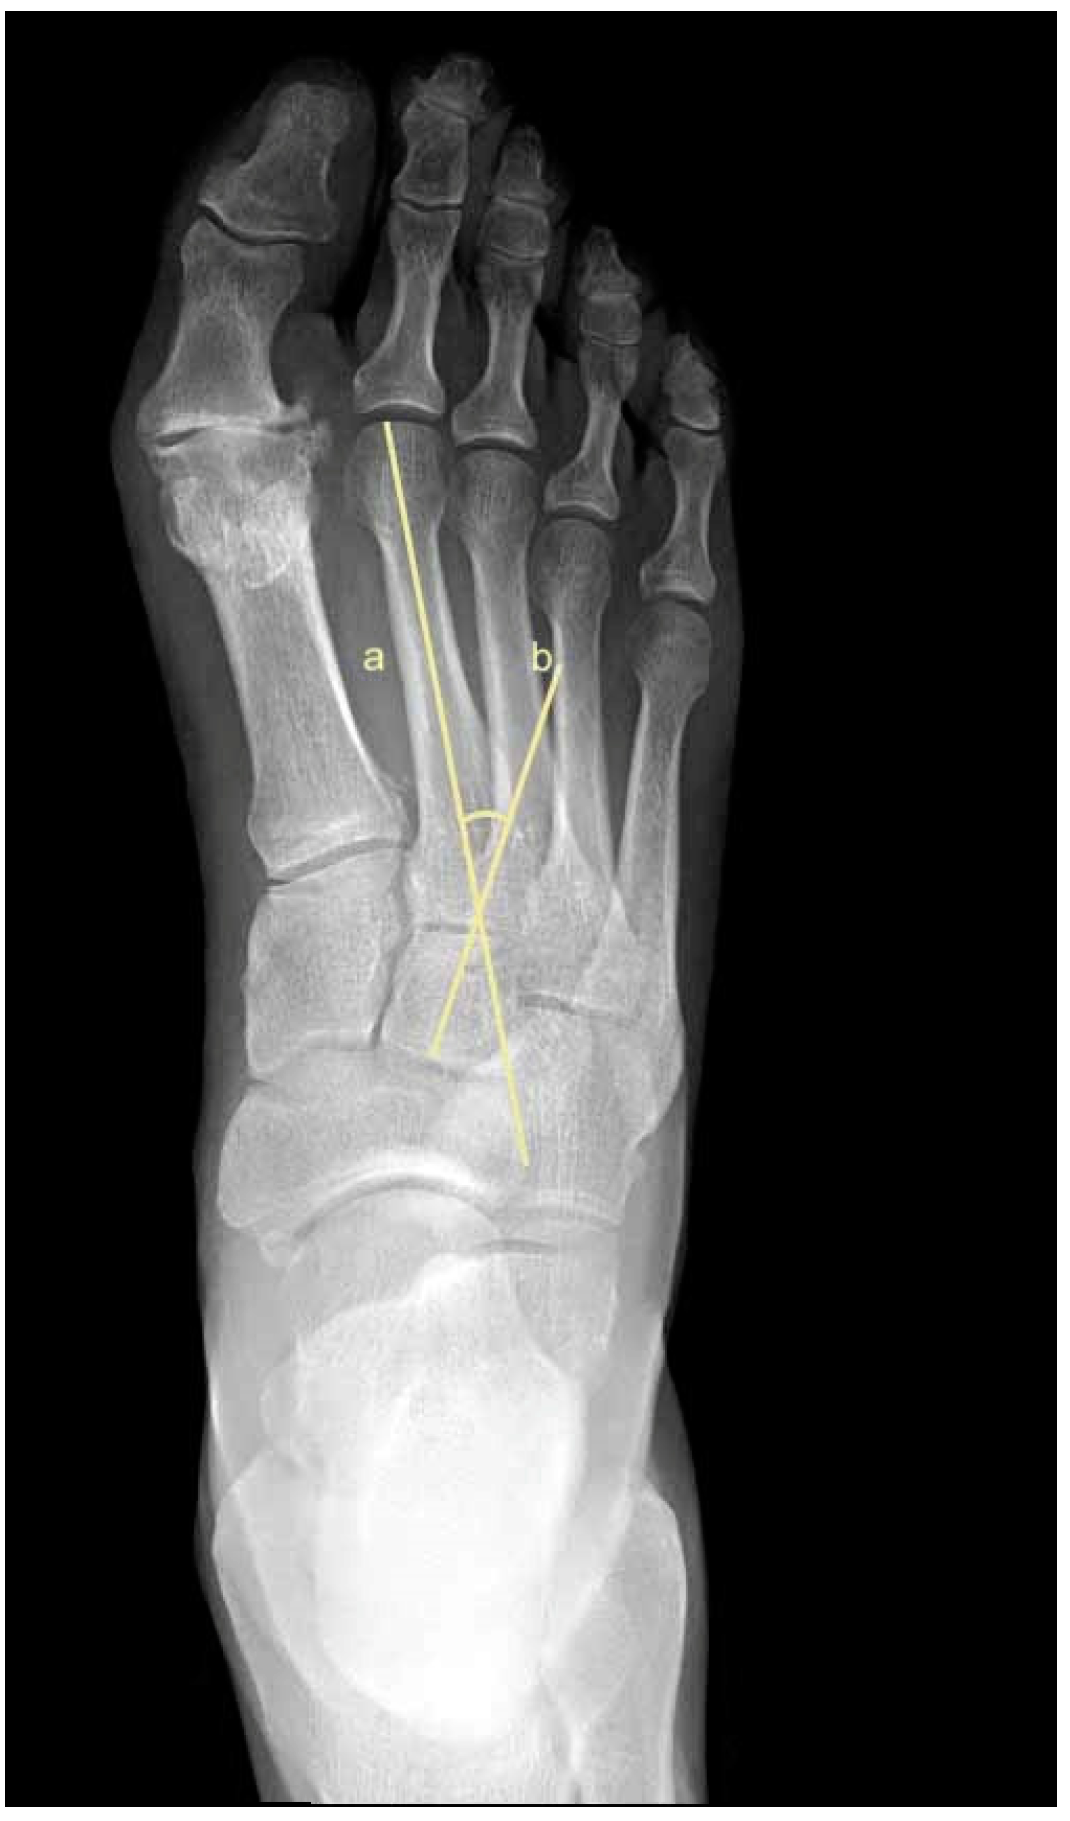

2.5. Metatarsus Adductus Measurements

- Sgarlato, T.E. Compendium of Podiatric Biomechanics; California College of Podiatric Medicine: San Francisco, CA, USA, 1971. [Google Scholar]

- Weissman, S.D. (Ed.) Biomechanically acquired foot types. In Radiology of the Foot; Williams and Wilkens: Baltimore, MD, USA, 1989. [Google Scholar]